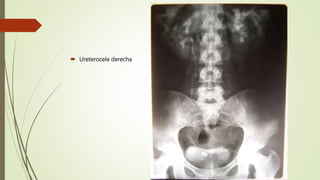

 Ureterocele derecha

 Doble sistema excretor